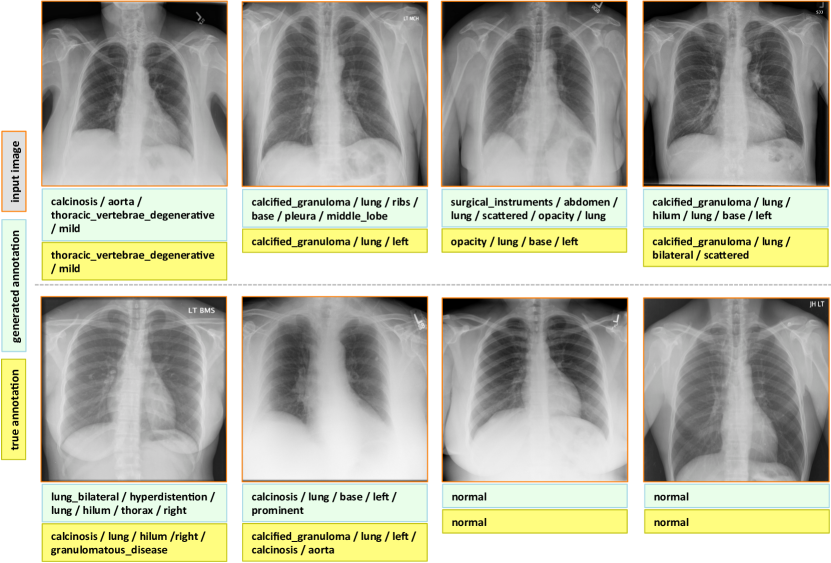

7.1 Evaluation

The final evaluated BLEU scores are provided in Table 5. We achieve better overall BLEU scores than those in Table 4 before using the joint image/text context. It is noticeable that higher BLEU-N () scores are achieved compared to Table 4, indicating that more comprehensive image contexts are taken into account for the CNN/RNN training. Also, slightly better BLEU scores are obtained using GRU on average and higher BLEU-1 scores are acquired using LSTM, although the comparison is empirical. Examples of generated annotations on the chest x-ray images are shown in Figure 6. These are generated using the GRU model, and more examples can be found in the supplementary material.

Appendix C More Annotation Generation Examples

More annotation generation examples are provided in Figures 10 and 11. Overall, the system generates promising results on predicting disease (labels) and its context (attributes) in the images. However, rare disease cases are more difficult to detect. For example, the cases pulmonary_atelectasis, spondylosis, and density (Figure 10), as well as foreign_bodies, atherosclerosis, costophrenic_angle, deformity (Figure 11) are much rarer in the data than calcified_granuloma, cardiomegaly, and all the frequent cases listed in Table 1 of the main paper.

Furthermore, the (left or right) location of the disease cannot be identified in a lateral view (obtained by scanning the patient from the side), as shown in Figure 11. Since our dataset contains a limited number of disease cases, we treat each x-ray image and report as a sample, and do not account for different views.

For future work, we plan to improve prediction accuracy by both (a) accounting for the different views, and (b) collecting a larger dataset to better account for rare diseases.